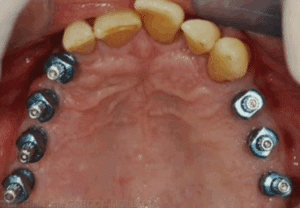

3) Terminologie

a) Pièces prothétiques :

La travée de bridge

La travée est constituée d’un ou plusieurs éléments intermédiaires, appelés pontiques.

Les connecteurs

b) Formes cliniques des bridges :

On distingue différentes formes de bridges en fonction de la topographie des piliers et des éléments intermédiaires (pontiques) :

Bridge "traditionnel"

- Fréquemment réalisé lorsque les piliers se situent de part et d’autre de l’édentement.